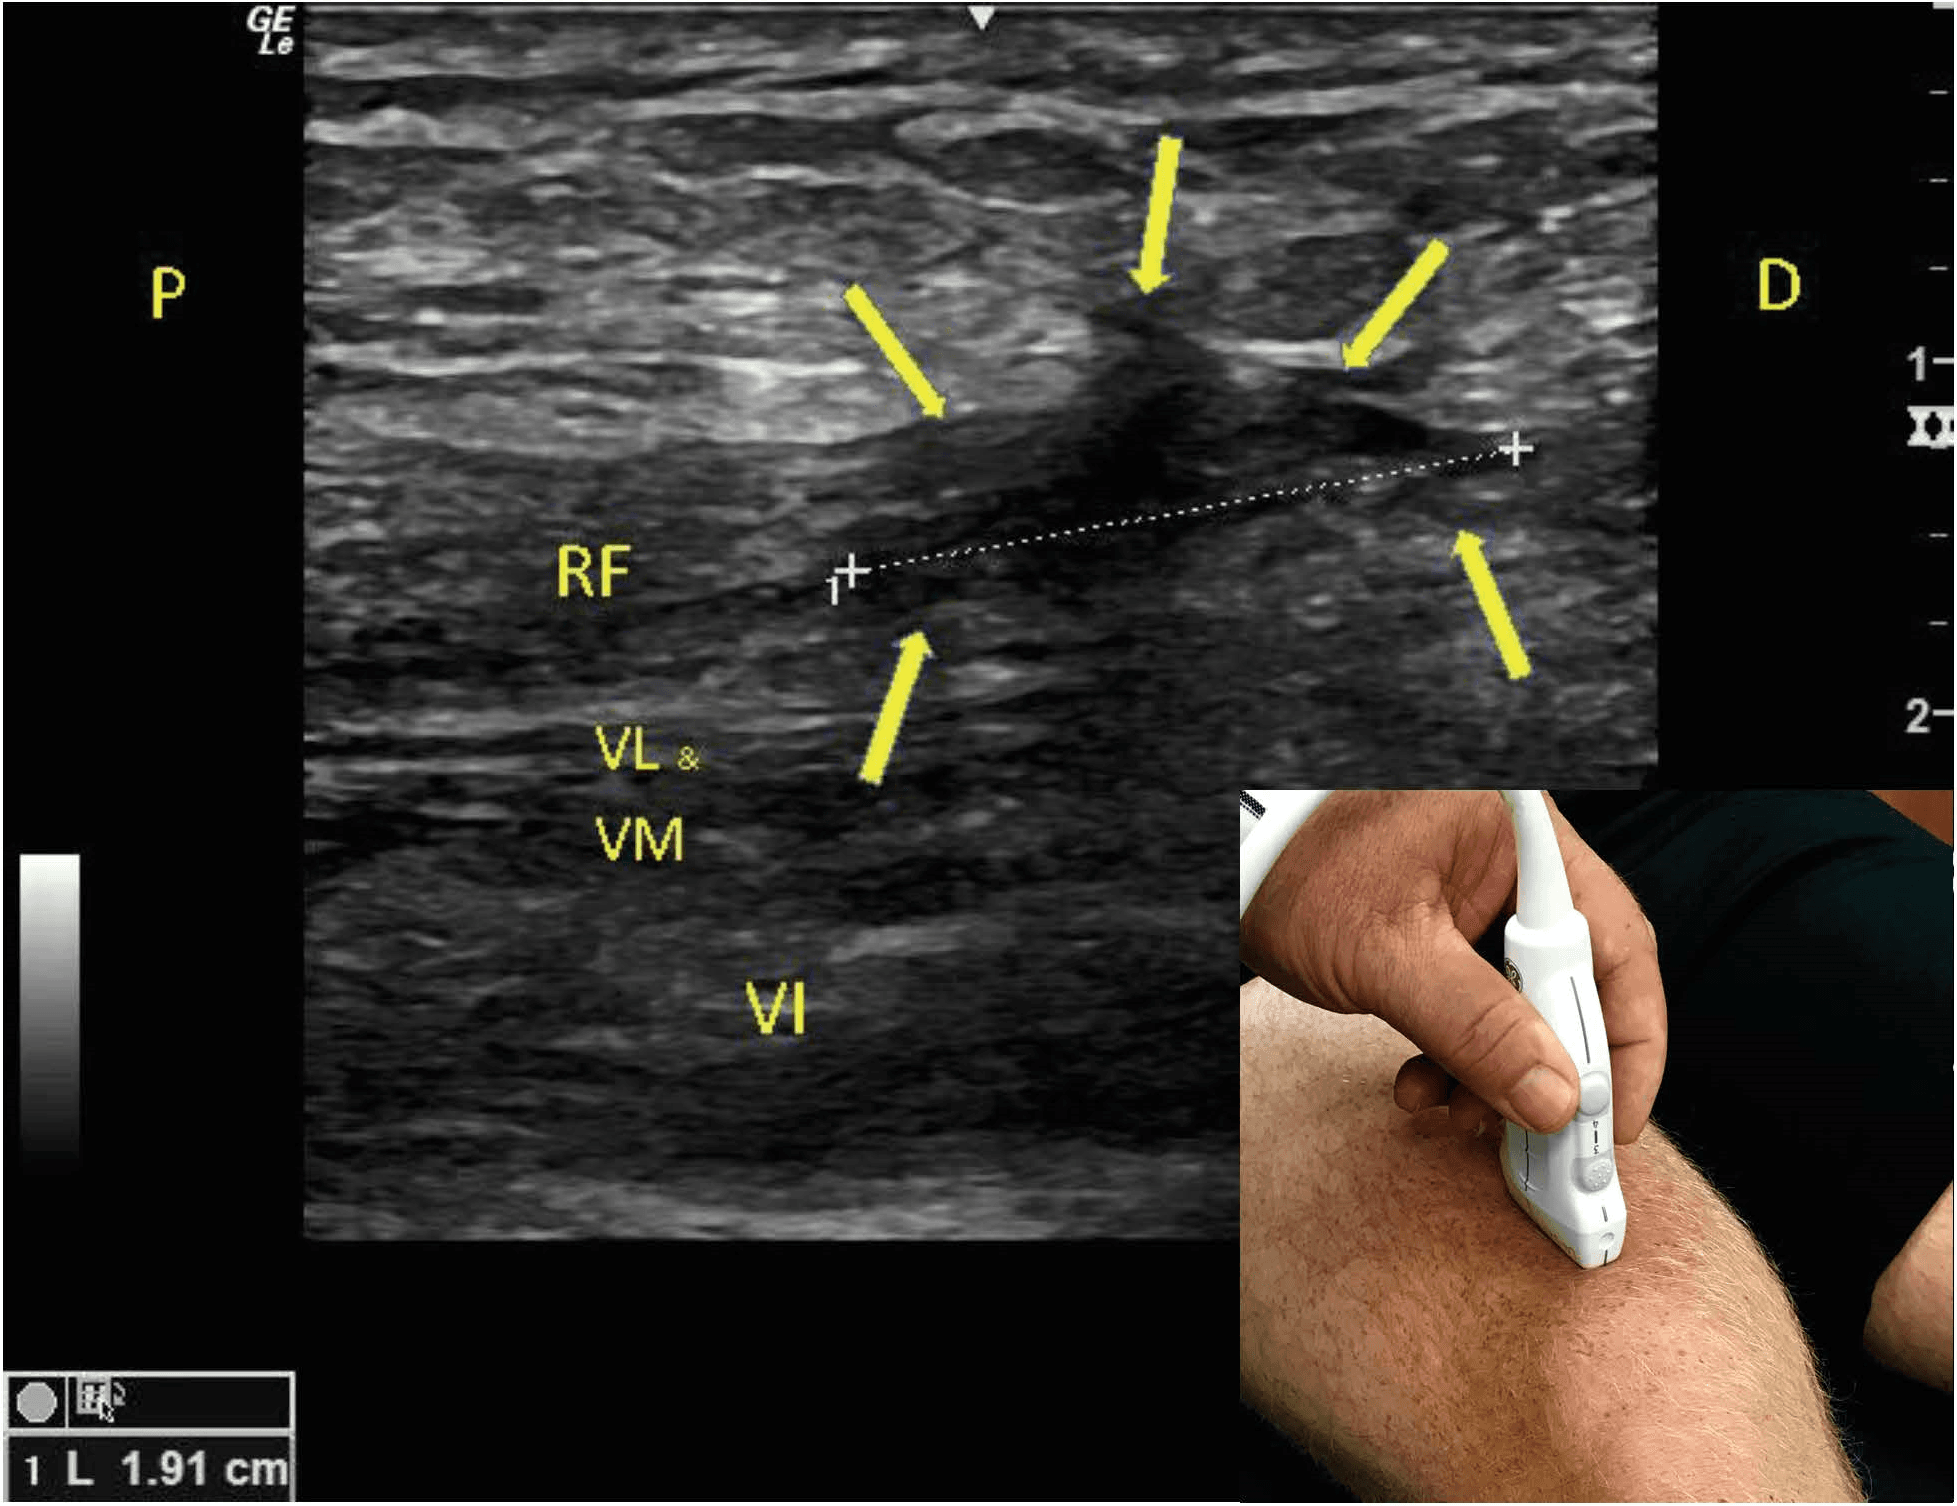

Quadriceps Tendon Ultrasound Quadriceps Tendonitis Mri Diagnosis is made clinically with. We examined this layered configuration on mr images to determine if it is relevant in the evaluation of the traumatized quadriceps tendon. The quadriceps tendon is a multilayered and laminated structure, as shown by anatomical specimens and mri scans. To confirm the diagnosis, your. For example, computed tomography (ct) or magnetic resonance imaging (mri) of. Quadriceps Tendonitis Mri.

Quadriceps Tendon Ultrasound Quadriceps Tendonitis Mri While this part of the examination can be painful, it is important to identify a quadriceps tendon tear. The quadriceps tendon is a multilayered and laminated structure, as shown by anatomical specimens and mri scans. For example, computed tomography (ct) or magnetic resonance imaging (mri) of the knee can exclude any acute bony injuries, meniscus tears, or ligament injuries. To. Quadriceps Tendonitis Mri.